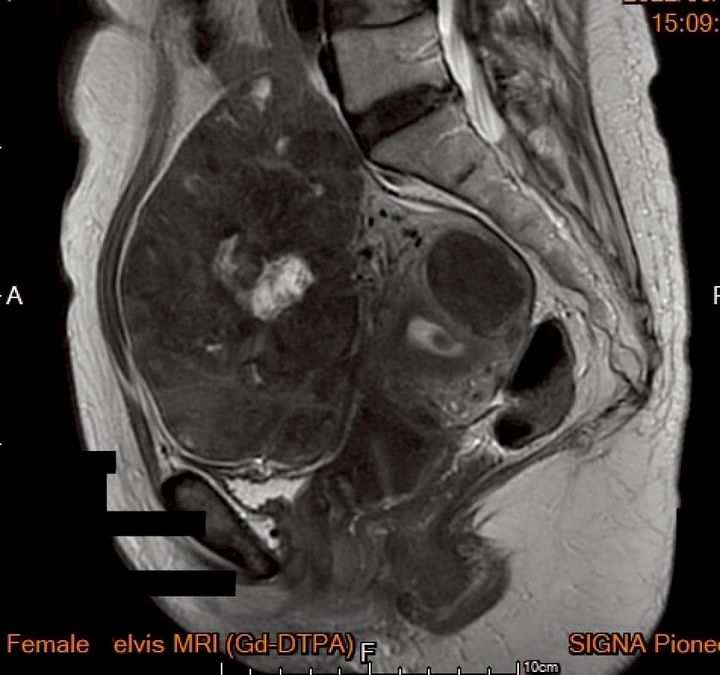

榜生婦幼聯盟菡生婦幼診所的曾宇泰院長提出了突破性的「二階式根除療法」,成功聯手海扶刀與內視鏡技術,有效擊退巨大子宮肌瘤。傳統的剖腹手術通常需要較長的恢復期,且對患者外觀產生影響。但隨著無創技術的進步,海扶刀已逐步應用於婦科手術中,不僅大幅減少手術創傷,還能顯著提升患者的術後生活質量。這項技術為子宮肌瘤患者帶來了全新的治療選擇!💪